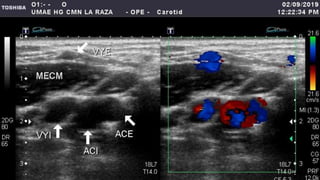

• 3. Identificación y

caracterización adecuada de

las arterias carótida externa

y de la carótida interna.

• 5. Se exploran las arterias

vertebrales.

– Primera rama de arteria

subclavia.

– Se localiza con el traductor

sobre la ACC angulando de

manera que entre se

visualicen la arteria y vena

vertebral entre las apófisis

transversas.

– Puede variar el tamaño y su

contribución relativa al flujo

de la arteria basilar.